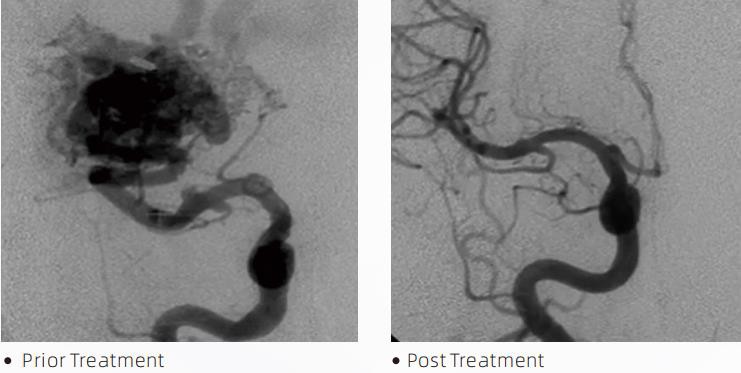

LavanTMLiquid Embolic System är en interventionell endovaskulär terapi för behandling av cerebrovaskulära missbildningar. Cerebrovaskulär missbildning avser en grupp av godartade eller maligna neurovaskulära avvikelser som kan leda till intrakraniell blödning, hjärninfarkt, cerebral ischemi och andra sjukdomar. Det flytande emboliseringssystemet är en medicinsk anordning som administreras genom enkel intravaskulär insättning, som emboliserar onormala hjärnblodkärl genom att injicera ett speciellt vätskematerial. Det flytande materialet bildar en kontrollerad vävnadsemboli i blodkärlen, vilket kan minska effekten av cerebrovaskulära missbildningar på patienter. En DMSO-kompatibel leveransmikrokateter som är indikerad för användning i neurovaskulaturen används för att komma åt emboliseringsstället. Lava flytande embolimedel är ett icke-vidhäftande flytande embolisystem som består av EVOH (etylenvinylalkohol) sampolymer löst i DMSO (dimetylsulfoxid) och suspenderat mikroniserat tantalpulver för att ge kontrast för visualisering under fluoroskopi. LavaTMfinns i tre produktformuleringar, LAVA-12, LAVA-18 och LAVA-34. LAVA-12: Rekommenderas vid matning av distala mikrokärl och genom små matare. LAVA-18: Rekommenderas när utfodring av pedikelinjektioner kommer att utföras nära nidus; LAVA-34: Rekommenderas för embolisering av högre flöde och större fistulösa komponenter.